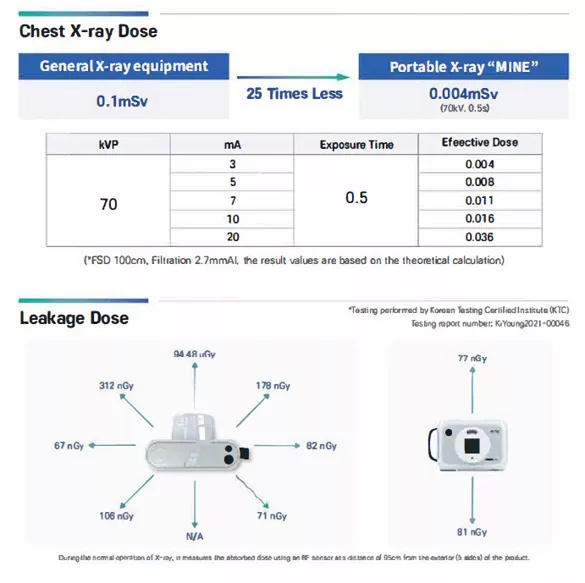

Επιπρόσθετα, εξοπλίσαμε τη συσκευή με τεχνητή νοημοσύνη (AI) για την αυτόματη βελτίωση της εικόνας. Αυτή η τεχνολογία επιτρέπει την ταχύτατη και ακριβή διάγνωση ακόμη και από απόσταση. Ταυτόχρονα, η ασφάλεια του ασθενούς αποτελεί την ύψιστη προτεραιότητα του συστήματος. Η έκθεση στην ακτινοβολία παραμένει ελάχιστη χάρη στα προηγμένα φίλτρα προστασίας.

Συγκεκριμένα, διαθέτει ειδικά φίλτρα για εγκυμοσύνη και παιδιατρικές εξετάσεις για μέγιστη προστασία. Επίσης, ο ενσωματωμένος αισθητήρας ασφαλούς απόστασης αποτρέπει την άσκοπη έκθεση του προσωπικού. Αξίζει να σημειωθεί ότι το σύστημα υποβλήθηκε σε αυστηρές δοκιμές τριών ετών. Κατά συνέπεια, έλαβε την επίσημη έγκριση FDA, αποδεικνύοντας την κλινική του αξία.

- Χαμηλή δόση ακτινοβολίας, σχεδόν 50.000 φορές χαμηλότερη από τα παραδοσιακά ακτινολογικά, εξασφαλίζοντας πιο ασφαλείς εξετάσεις, ιδιαίτερα για ευπαθείς ομάδες, όπως τα παιδιά.